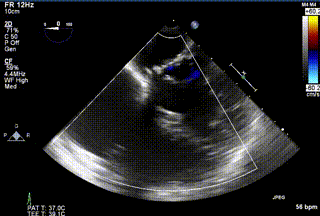

2021年12月24日,復(fù)旦大學(xué)附屬中山醫(yī)院葛均波院士團(tuán)隊(duì)成功應(yīng)用LuX-Valve Plus為一例極重度三尖瓣反流(TR)合并房顫、房缺的患者完成了經(jīng)血管三尖瓣置換術(shù),這是在前基礎(chǔ)上,本周完成的第三例經(jīng)血管三尖瓣置換手術(shù),葛均波院士、周達(dá)新教授等與心外科魏來教授、賴顥教授,心超室的潘翠珍教授、李偉教授及麻醉科的郭克芳教授共同完成了本周手術(shù),均獲得圓滿成功!患者術(shù)后超聲顯示無TR,臨床癥狀明顯改善。本周手術(shù)的成功也為L(zhǎng)uX-Valve Plus救治性臨床研究添上了濃墨重彩的一筆。

三例患者入院后,葛均波院士團(tuán)隊(duì)周達(dá)新教授、潘文志教授、張?jiān)床┦俊㈥惿┦考靶某业呐舜湔浣淌?、李偉教?/strong>對(duì)患者的情況進(jìn)行詳細(xì)評(píng)估和討論,最終決定為三例患者選擇LuX-Valve Plus40mm、50mm和50mm型號(hào)的瓣膜進(jìn)行手術(shù)治療。手術(shù)后即刻拔除氣管插管,術(shù)后患者三尖瓣反流癥狀得到顯著改善,復(fù)查心超結(jié)果顯示人工三尖瓣瓣膜支架固定穩(wěn)定,瓣葉關(guān)閉形態(tài)未見異常,未見明顯反流。